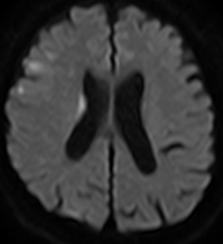

当院で行われた血栓除去術の実際の症例をお示しします。1例目は65歳男性、自宅にて動けなくなっているところを発見されました。軽度意識障害、重度の左片麻痺にて当院に救急搬送、NIHSS17点、心房細動を認めました。頭部MRI(図4)にて右大脳半球に矢印のように虚血巣の出現あり、MRA(図5)にて矢印のように右中大脳動脈の描出なく、緊急にて血管撮影を施行しました。バルーン付きのガイディングカテーテルを入れて、血栓より遠位にマイクロカテーテルを入れて、血栓の遠位からステント(Trevo provue 4×20mm)を展開後、血栓を回収しました。その後の撮影では閉塞していた血管はTICI2bまで再開通しており、治療直後から患者さんの左片麻痺は改善を認め、翌日のMRIでも梗塞巣は広範とならず、治療17日後に自宅退院しました。現在は社会復帰しており、元のお仕事にも戻っております。(図6、7、8、9参照)

図4:MRI拡散強調画像 |